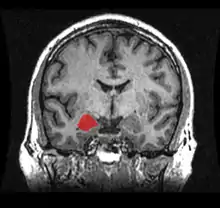

أظهرت دراسات التصوير العصبي لمرضى اضطراب الشخصيّة الحدّي وجود انحسارات في مناطق في الدماغ المسؤولة عن الضبط والتحكم بردود الأفعال تجاه الكرب والعواطف، والتي تكون في منطقة الحصين والقشرة الجبهيّة الحجاجيّة واللوزة الدماغيّة بالإضافة إلى مناطق أخرى.[52] في عدد محدود من الدراسات جرى استخدام تقنيّة مطيافيّة الرنين المغناطيسي النووي من أجل دراسة التغيّرات في تراكيز المستقلبات العصبيّة في مناطق محدّدة في الدماغ لدى المصابين باضطراب الشخصيّة الحدّي، وخاصّة مركّبات مثل ن-أسيتيل الأسباراتات، والكرياتين، والمركّبات المتعلّقة بالغلوتامات والمركّبات الحاوية على الكولين.[52]

- الحصين

يكون الحصين ذو حجم أصغر عند الناس المصابين باضطراب الشخصيّة الحدّي مقارنة مع الأشخاص الذين لديهم اضطراب الكرب التالي للصدمة؛ ولكن بالمقابل، فإنّ مرضى BPD على العكس من PTSD تكون لديهم اللوزة الدماغية لديهم أيضاً ذات حجم أصغر.[53]

- اللوزة الدماغية

تكون اللوزة الدماغيّة عند المصابين باضطراب الشخصيّة الحدّي صغيرة وذات فعاليّة أكبر.[53] كما وجدت ظاهرة صغر حجم اللوزة الدماغية عند الأشخاص الذين لديهم اضطراب وسواسي قهري.[54] في دراسة أخرى، أظهرت الأبحاث وجود نشاط قوي غير طبيعي في اللوزة اليسرى عند المصابين باضطراب الشخصيّة الحدّي عندما يمرّون بتجربة تؤدي إلى إظهار مشاعر سلبيّة.[55] بما أنّ للوزات الدماغيّة دوراً في العديد من المشاعر (من ضمنها السلبيّة)، فإنّ النشاط غير الطبيعي يمكن أن يفسّر مدى قوة واستمرارية الشعور بالخوف والغضب والخزي عند المصابين باضطراب الشخصيّة الحدّي، بالإضافة إلى حساسيّتهم العالية لإظهار تلك المشاعر عند آخرين.[53]

- القشرة أمام الجبهية

إنّ القشرة أمام الجبهيّة تميل لأن تكون أقلّ فاعليّة عند المصابين باضطراب الشخصيّة الحدّي، خاصّة عند استرجاع ذكريات الهجران.[56] تحدث ظاهرة عدم الفعاليّة النسبيّة هذه في القشرة الحزاميّة الأماميّة اليمينيّة (في باحات برودمان 24 و 32).[56] بما أن للقشرة أمام الجبهيّة دوراً في ضبط الهيجان العاطفي، فإنّ عدم فعاليّتها النسبيّة يمكن أن يشرح الصعوبات التي يعانيها المصابون باضطراب الشخصيّة الحدّي في ضبط مشاعرهم وردود أفعالهم تجاه الكروب.[57]